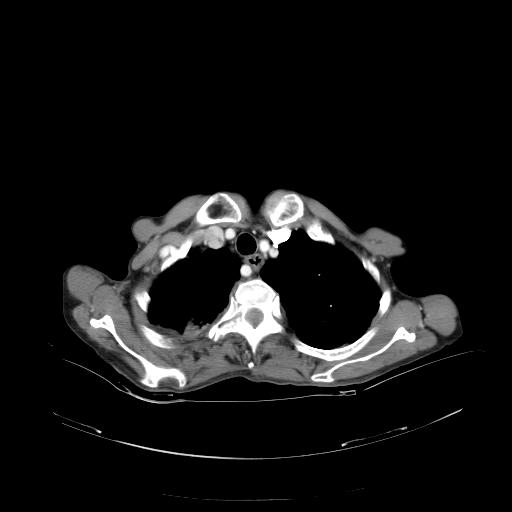

女,72岁,咳嗽一周余,突发右下肢无力二天。

pe:bp-140、80mmhg,精神可,伸舌居中,右上肢肌力正常,右下肢肌力0级,巴氏征+

来院做头颅+胸部ct平扫

遂加作增强:

胸部病变平扫35hu,增强强化至70hu

这个病人首先是胸部病变的定位到底是肺内还是肺外。仔细观察块影位于胸膜下,与胸膜间有透亮带,且近端血管未见明显推移而是引流样改变,形态分叶,说明这个病灶位于肺内胸膜下。很可能是腺癌,腺癌最易致颅内高密度转移灶。局部胸膜有侵犯。

本例颅内见多发大小不等高密度灶,有强化及水肿;另外,胸锁关节层面可能是第四胸椎及右侧肋骨起始部骨质欠连续,椎旁软组织肿胀,建议调骨窗观察。

诊断:右下肺癌伴颅内、胸椎、肋骨转移可能性最大。